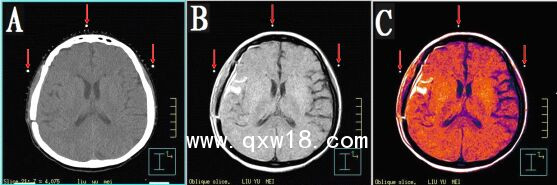

本產(chǎn)品主要適用于不同模態(tài)圖像引導(dǎo)下放療時定位,定點經(jīng)皮穿刺活檢或積液抽吸引流,不同模態(tài)間圖像融合控制點配準(zhǔn)等。

2.??多角度掃描小球,圖像均為高亮度圓點狀,無放置角度限制。

3.??同一定位貼,在多種模態(tài)掃描下成像均能顯示為點狀,可用作圖像融合的共同配準(zhǔn)控制點,大小、位置一致,方便全身或軀段臟器異機圖像融合,精度高,易開展新的臨床應(yīng)用。

CT和MR通用型:具有同一個定位球在CT掃描高密度、MR常規(guī)掃描高信號的特點,主要用于

CT/MR圖像融合,更換掃描設(shè)備,不需要更換標(biāo)記點。型號MK⊙CT/MR,每盒三貼;